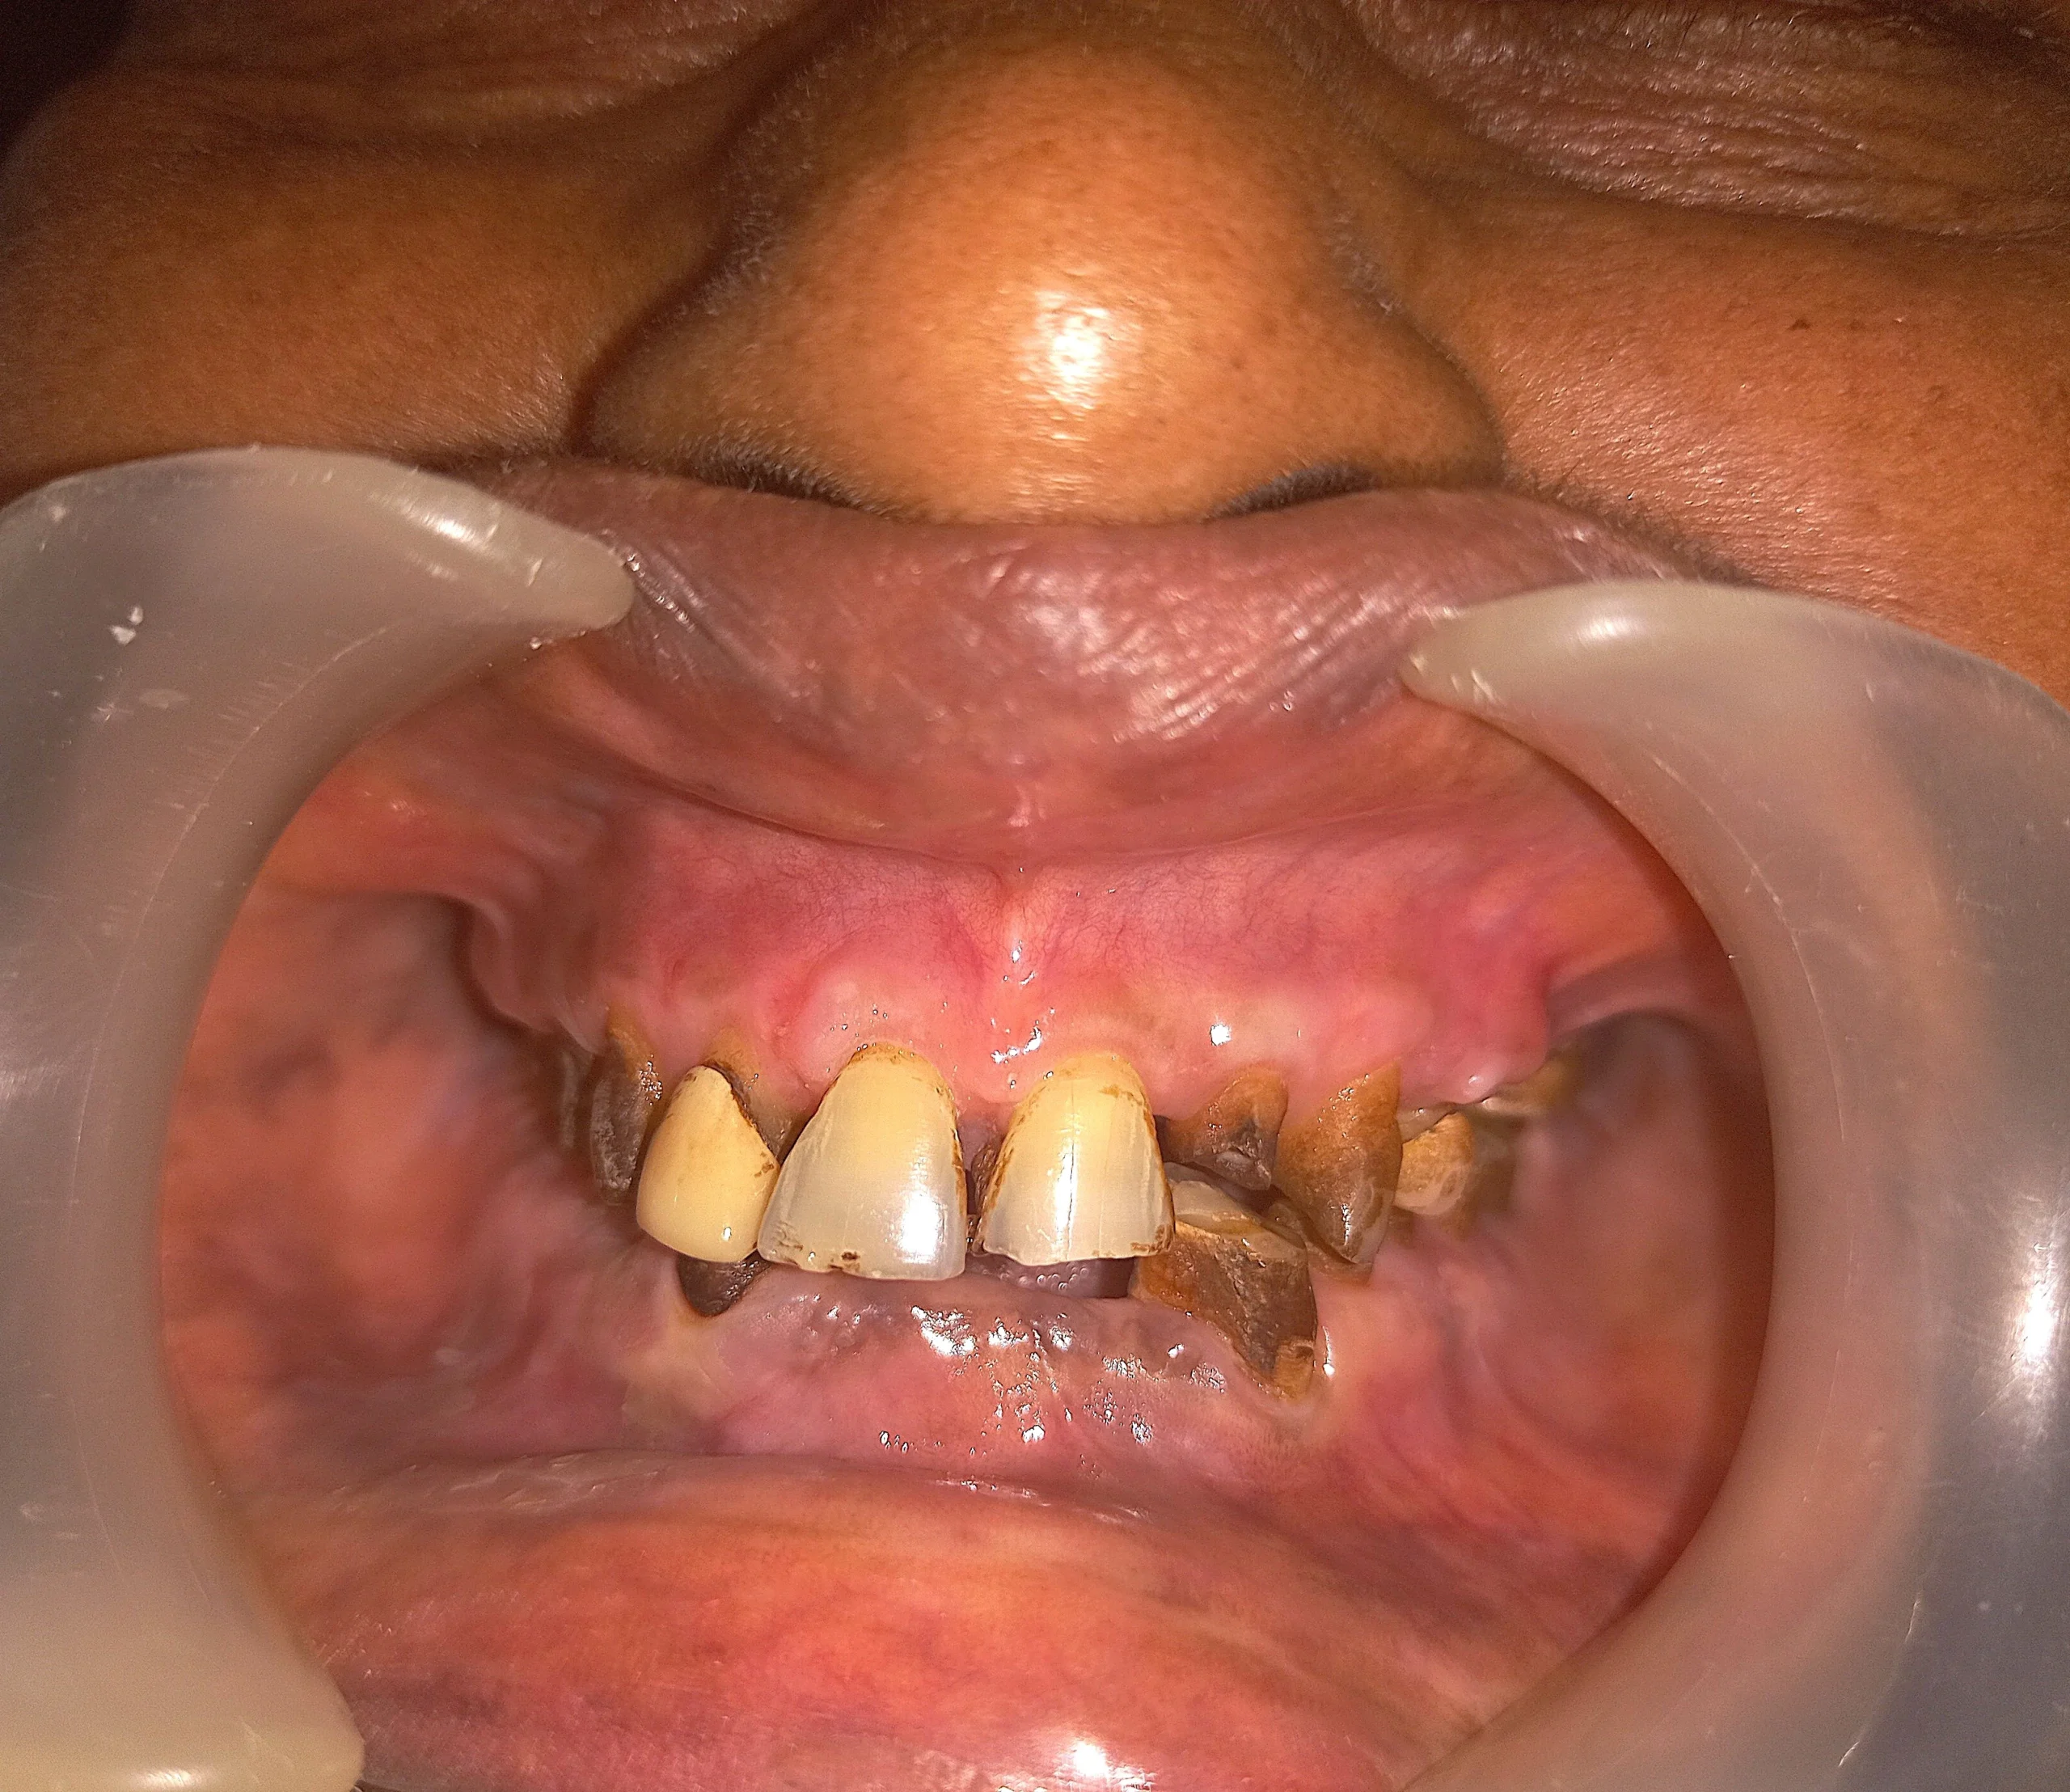

This elderly patient had been chewing supari for many years. Over time, her teeth wore down unevenly, her bite collapsed, and chewing food became extremely difficult.

Facial height reduced, jaw position changed, and daily eating became tiring and uncomfortable.

A gentle, step-by-step Full Mouth Reconstruction plan was created to restore bite height, improve chewing efficiency, and stabilize remaining teeth — without aggressive surgery.

Age is never the deciding factor. Planning, precision, and comfort are.

Collapsed bite due to supari chewing

Before: collapsed bite and difficulty in eating

Completely worn out teeth